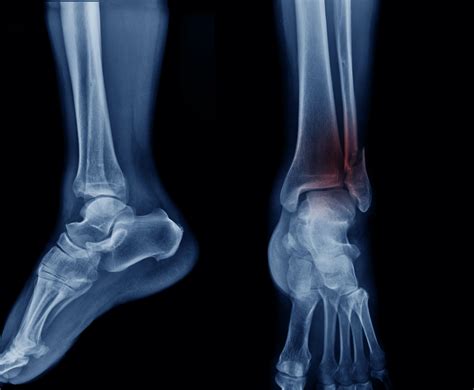

Experiencing a sudden, sharp pain in your ankle after a fall or an awkward twist can be a frightening experience. One of the most critical steps in diagnosing the severity of this injury is obtaining a broken ankle Xray. This medical imaging test is the gold standard for determining whether the bone is fractured, the extent of the damage, and the appropriate course of treatment. Whether you are dealing with a simple hairline fracture or a more complex break involving multiple bones, understanding what to expect during the imaging process and how to interpret the results is essential for your recovery journey.

When you visit an urgent care clinic or an emergency room with ankle pain, the physician will first perform a physical examination. However, even the most experienced doctor cannot confirm a fracture just by looking at the surface. A broken ankle Xray is necessary to visualize the internal structure of the joint. It provides a clear, two-dimensional image of the tibia, fibula, and talus, allowing medical professionals to rule out or confirm a break.

By securing an image, the radiologist or orthopedist can identify the exact location and pattern of the break. This accuracy is vital because different types of fractures require vastly different treatments, ranging from simple immobilization in a walking boot to surgical intervention with plates and screws.

Once the images are captured, they are reviewed by a radiologist. The broken ankle Xray will reveal whether there is a cortical breach—the medical term for a break in the bone's outer shell. The report will describe the type of fracture, which helps the orthopedic surgeon plan the treatment.